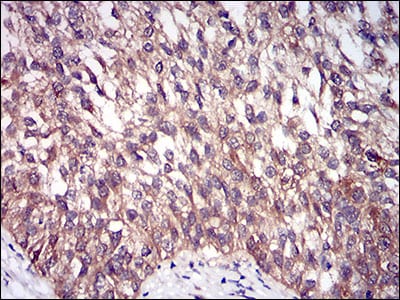

| IHC | 1/200 - 1/1000 | Human,Mouse,Rat |

3. **文献名称**:DIS3L2 promotes colorectal cancer progression through regulating cell cycle-related proteins

**作者**:Wang Y, et al.

**摘要**:通过免疫组化技术分析结直肠癌组织,发现DIS3L2蛋白高表达与患者不良预后相关,功能实验表明其通过调控细胞周期蛋白促进肿瘤增殖,抗体用于组织定位及蛋白水平检测。